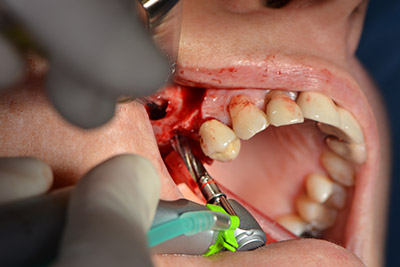

An absorbable membrane was used as the barrier in the buccal direction and covered the augmentation. Finally, saliva-proof sutures were placed (Fig. 15 to 19).

Augmentation with autologous bone

Image 15

Image 16